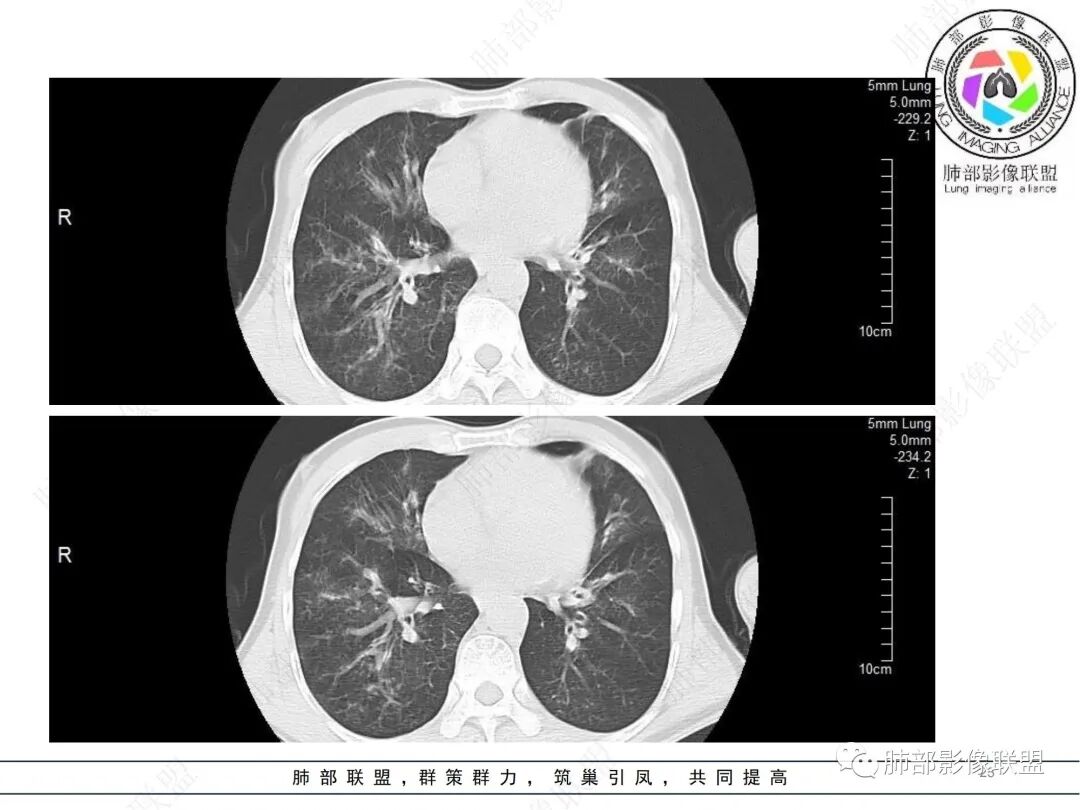

58岁男性,咳嗽胸闷3天,咳较多褐粘液痰,无发热。有2型糖尿病病史。白细胞与中性粒细胞升高。CRP升高。鳞状上皮细胞癌抗原轻度升高。结核T细胞免疫斑点实性阳性。肺炎支原体、衣原体IgG轻度升高。支气管镜显示支气管炎性改变、右肺下叶背段管腔狭窄。2.影像特点:

2022.6.24CT显示两肺弥漫性段、亚段支气管壁增厚(两肺各叶都累及),增厚的支气管壁外可见沿着支气管分布的渗出、实变影。另外远端肺内亦可见多发树芽影、结节影,其边界欠清晰。右肺下叶基底段局部胸膜下亦可见小斑片影,边界不清。2022.6.27CT显示两肺增厚的支气管壁外的渗出实变影明显增多、范围更广。远端肺内病灶亦增多、范围增大。部分位于胸膜下的病灶可见侧向融合趋势。3.病例分析:

中老年男性,咳嗽咳痰胸闷3天就诊,急性过程。有糖尿病基础。实验室检查炎症指标明显升高。结合影像学气道密切相关,首先考虑感染性病变。

影像学病灶双肺分布,支气管广泛增厚,较少见于普通社区肺炎,而更多见于气道侵袭性曲霉病。病原学检查证实烟曲霉感染的存在。